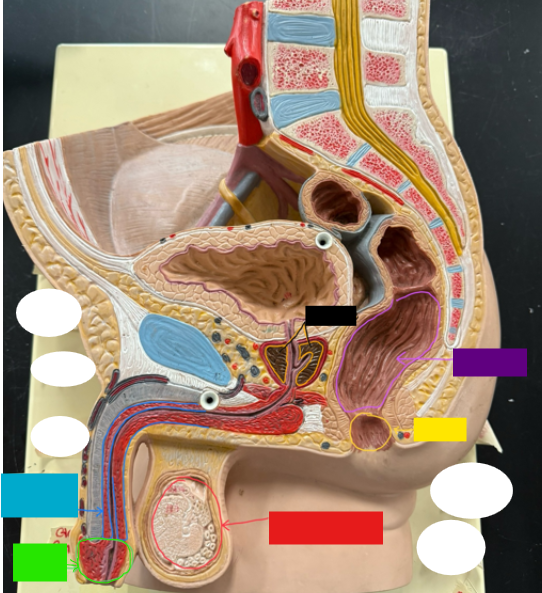

What is the name of the red box?

Ureter

What is the name of the red box?

Vas deferens

What is the name of the yellow box?

Seminal vesicle

What is the name of the blue box?

Prostate

What is the name of the light green box?

Epididymis

What is the name of the light blue box?

Prepuce

What is the name of the blue box?

Corpus spongiosum

What is the name of the light green box?

Glans penis

What is the name of the red box?

Seminiferous tubules

What is the name of the black box? X2

Prostate

What is the name of the purple box?

Rectum

What is the name of the yellow box?

Anus

What is the name of the red box?

Scrotum

What is the name of the orange box?

Corpus cavernosum

What is the name of the light blue box?

Spongy urethra

What is the name of the red box?

Prostatic urethra

What is the name of the pink box?

Ejaculatory duct

What is the name of the yellow box?

Membranous urethra

What is the name of the brown box?

Testis